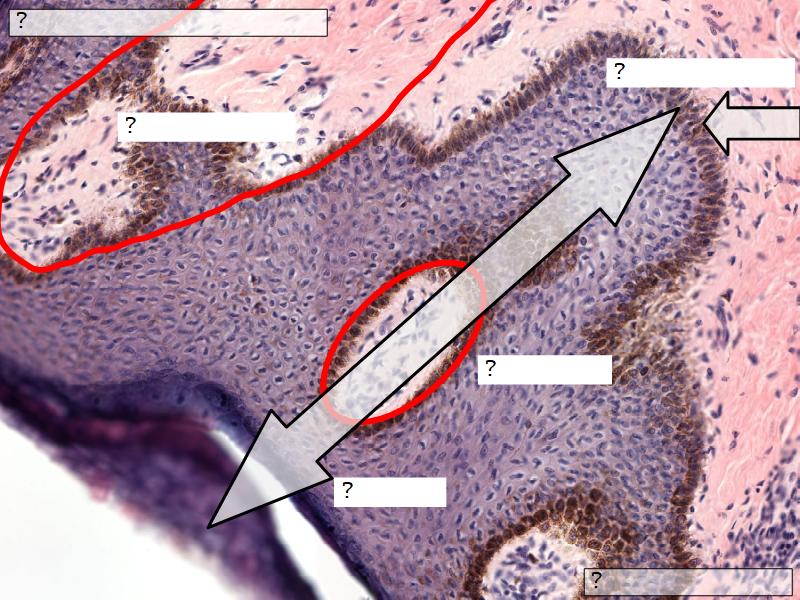

What are the main morphological features of the nipple?

(4)

Morphology

- Covered with skin

- Consists of dense collagenous connective tissue

- Interlaced with smooth muscle fibres

- Contains openings of lactiferous ducts

Skin

- Keratinized stratified squamous epithelium

- Sebaceous glands

Stroma

- Collagenous connective tissue

- Irregular dense connective tissue

- Smooth muscle

- Fibres and bundles

- Lactiferous sinusses

- Stratified cuboidal epithelium